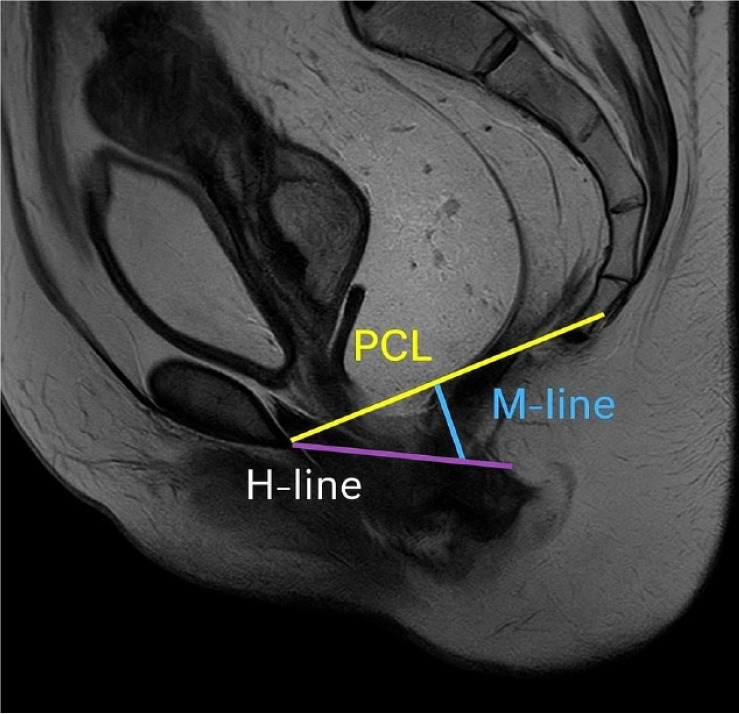

Results: Pelvic floor descent and anorectal junction descent were the most frequent findings, each present in 94.7% of cases. Rectocele was observed in 78.9% of patients, while vaginal or uterine prolapse was seen in 59.4% of females. Less common abnormalities included paradoxical contraction (7%), and there were no cases of sigmoidocele. Functional measurements showed significant differences in pelvic floor dynamics between rest and defecation, particularly in the H-line, M-line, and descent of pelvic organs (P < 0.05).